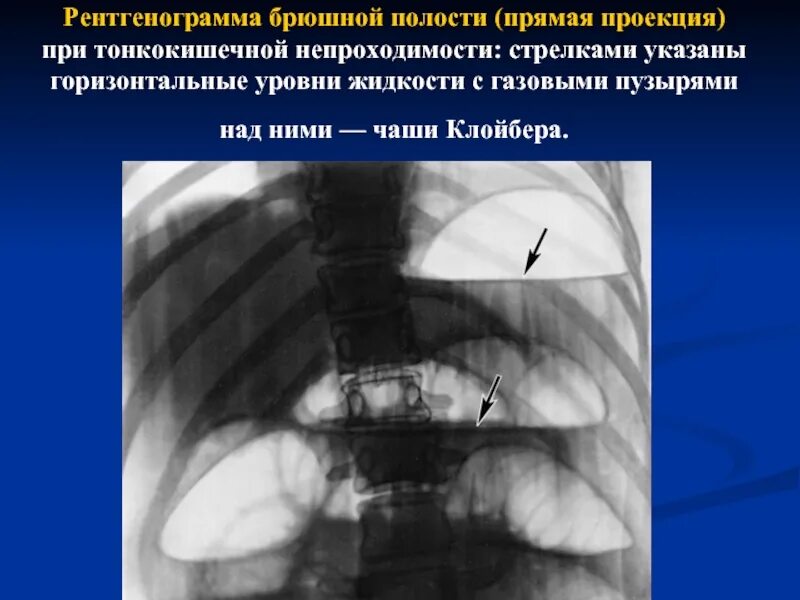

Симптом чаши